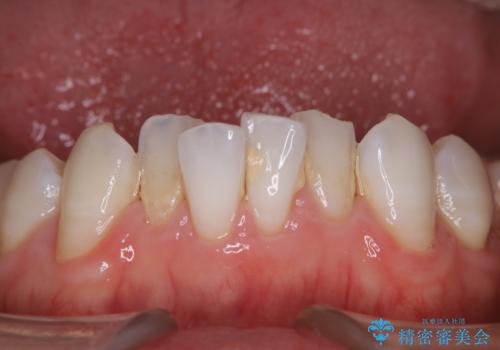

1年ぶりにコーヒーによる着色落とし PMTC